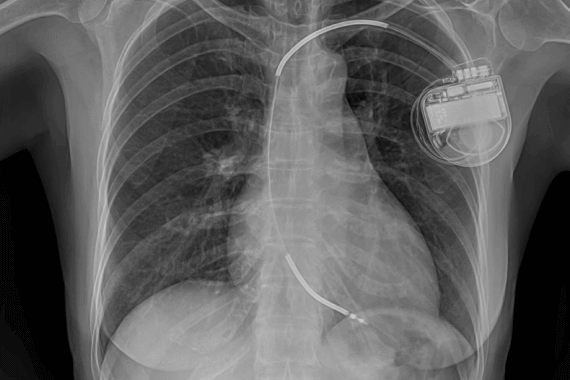

Pacemakers are implantable devices used to regulate and maintain a normal heart rhythm in patients with certain cardiac conditions.

These procedures involve the placement of a small electronic device, called a pacemaker, in the chest or abdomen to regulate the heart's electrical activity.

During the procedure, a small electronic device is implanted in the chest or abdomen. The device consists of one or more leads (thin wires) that are placed in the heart chambers or blood vessels.